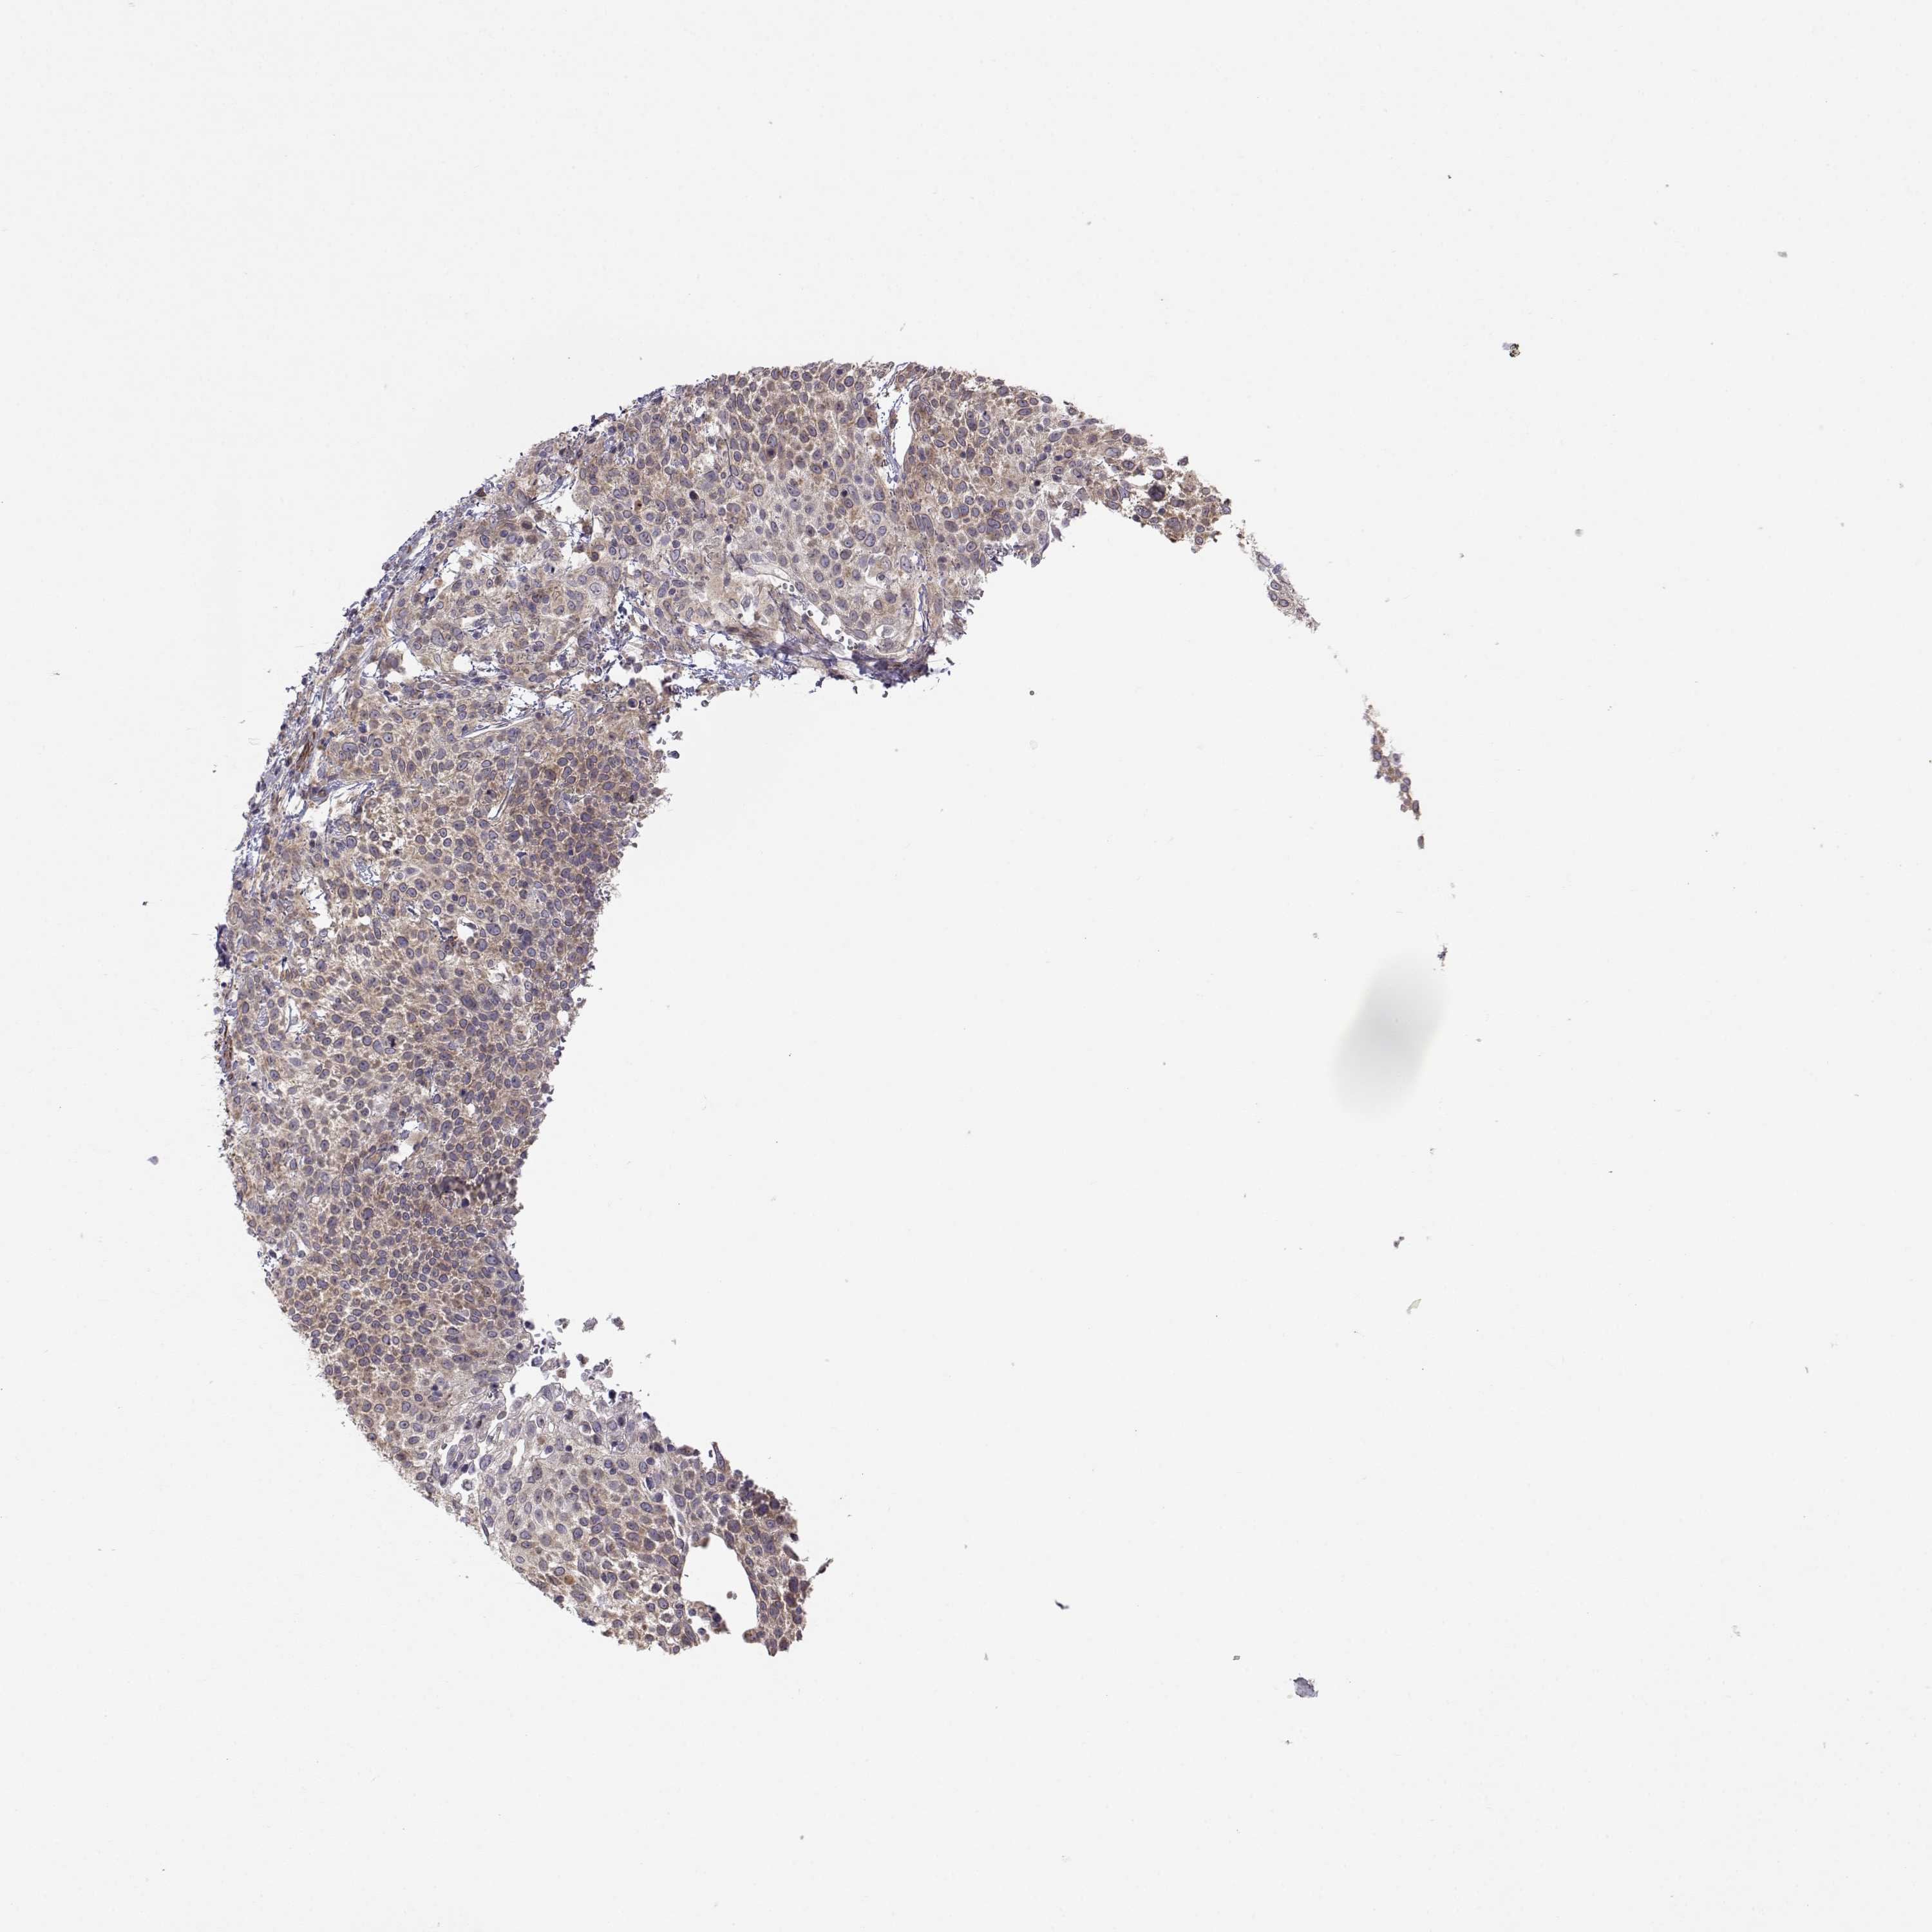

CERVICAL CANCER - Protein expressioni

A mouse-over function shows sample information and annotation data. Click on an image to view it in a full screen mode. Samples can be filtered based on level of antibody staining by selecting one or several of the following categories: high, medium, low and not detected. The assay and annotation is described here.

Note that samples used for immunohistochemistry by the Human Protein Atlas do not correspond to samples in the TCGA dataset.

Antibody stainingi

Antibody staining in the annotated cell types in the current human tissue is reported as not detected, low, medium, or high, based on conventional immunohistochemistry profiling in selected tissues. This score is based on the combination of the staining intensity and fraction of stained cells.

Each image is clickable and will lead to virtual microscopy that enables deeper exploration of all samples and also displays staining intensity scores, fraction scores and subcellular localization as well as patient and tissue information for each sample.

Antibody HPA073653

Staining

High

Medium

Low

Not detected

Intensity

Strong

Moderate

Weak

Negative

Quantity

>75%

75%-25%

<25%

None

Location

Nuclear

Cytoplasmic/membranous

Cytoplasmic/membranous,nuclear

Squamous cell carcinoma, NOS

Adenocarcinoma, NOS